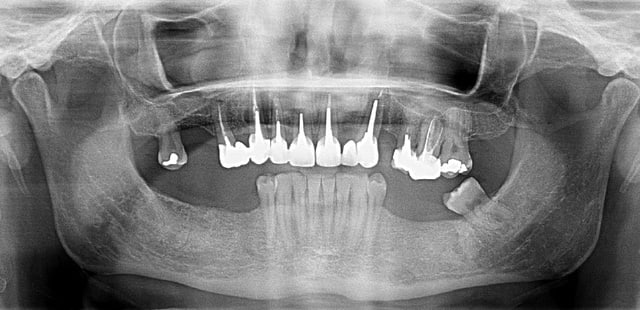

Quelques radios d'un cas en cours de traitement.

Aucun signe d'infection, pas de voussure, sauf une fistule en distal de la 13 qui apparaitrait régulièrement.

A votre avis la 12 peut elle être a l'origine des 2 lésions.

Si c'est le cas, l'extraction de la 12 pourait elle permettre de sauver la 13.

Qui est pour tout extraire (11 12 13)?

Une scanner pourrait-il être utile pour tenter d'en sauver une, afin de détemriner l'origine de la lésion ?

Je n'ai que la pano pour juger mais quand on regarde l'état paro de la 23 (avec une 22 en extension...) et l'apex de 26.... + 13 + 12 + syndrome du lapin => extraction et plan de traitement prothétique.